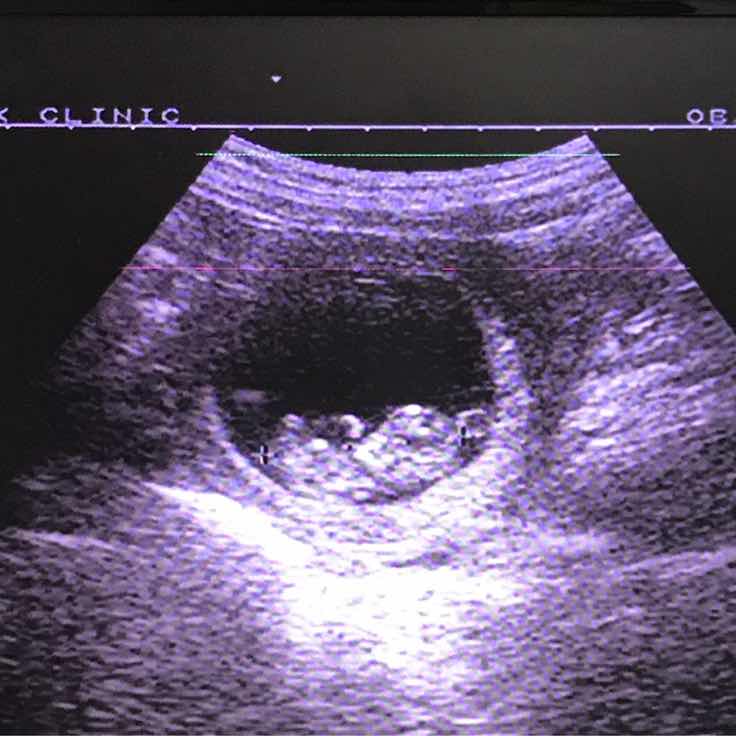

อายุครรภ์ 12 สัปดาห์...มีใครเห็นแขน-ขา ชัดๆ บ้างคะ

แม่ท้องท่านไหนเห็นแขน-ขา ของลูกชัดๆ จากภาพ ultrasound บ้างคะ ของเราตอน ultrasound อายุครรภ์ 12 สัปดาห์ 5 วัน ได้ภาพออกมาตามรูปเลย...เราหาแขนลูกไม่เจออ่า ?...ใครพอดูออกบ้างคะ...วานบอกให้คลายกังวลหน่อยค่าาา

ในรูปเราก็เห็นแขนน้องขาน้องอยู่นะคะ แต่ยังไม่เห็นมือ อายุครรภ์ยังเล็กมองยากอยู่ค่ะ

12wยังไม่พัตนาเต็มที่ค่ะแต่เห็นงอกมานิดๆแล้วนะค่ะไม่ต้องกังวลค่ะ

คร่า...ขอบคุณนะคะ นี่พยายามดูรูปลูกตัวเองอยู่หลายรอบ พลิกแล้วพลิกอีก ก็ยังดูไม่ค่อยออก...น่าจะเป็นตามที่คุณแม่บอกค่ะ...เดือนหน้าไป ultrasound ใหม่ น่าจะเห็นแขน-ขาน้องชัดขึ้น 😊